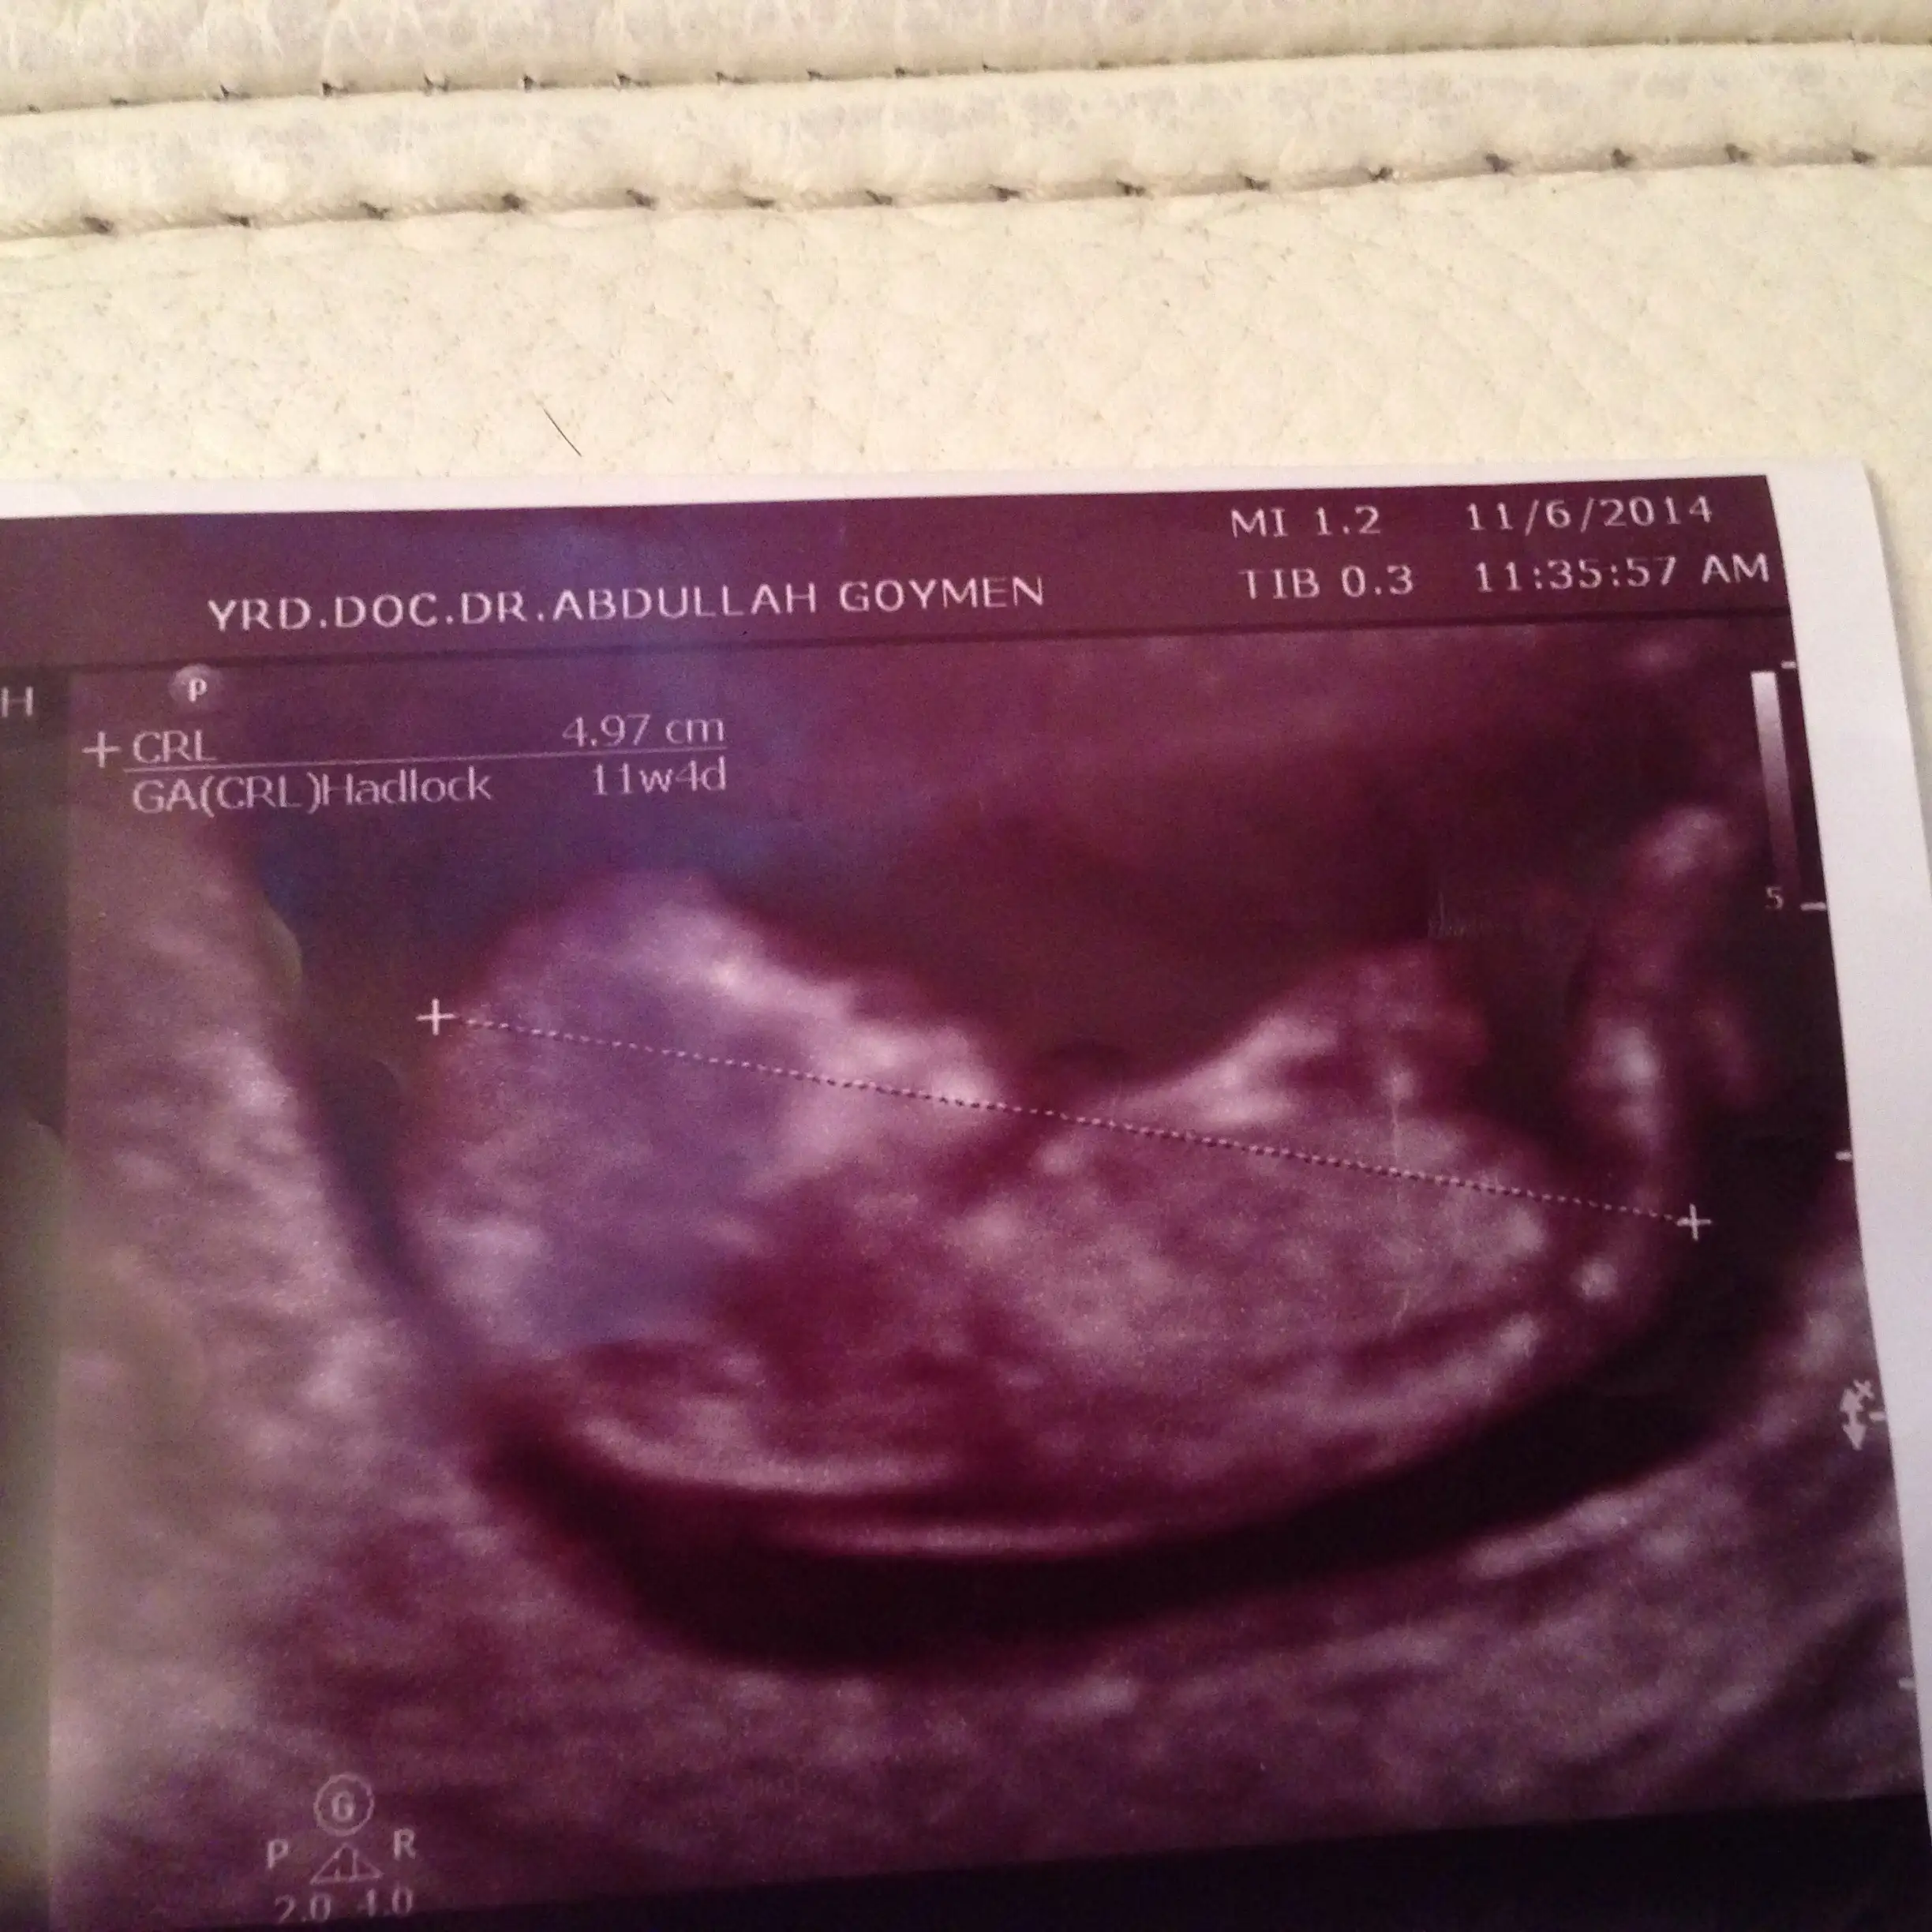

İlk iki görüntü ense kalınlığına bakmak için girdiğim ultrason görüntüleri alttaki diğer 2 görüntüyse normal doktor kontrolündeki ultrason görüntüleri ve ikisi de aynı gün ve tam 12 haftalıkken ve tekrar teşekkür ediyorum